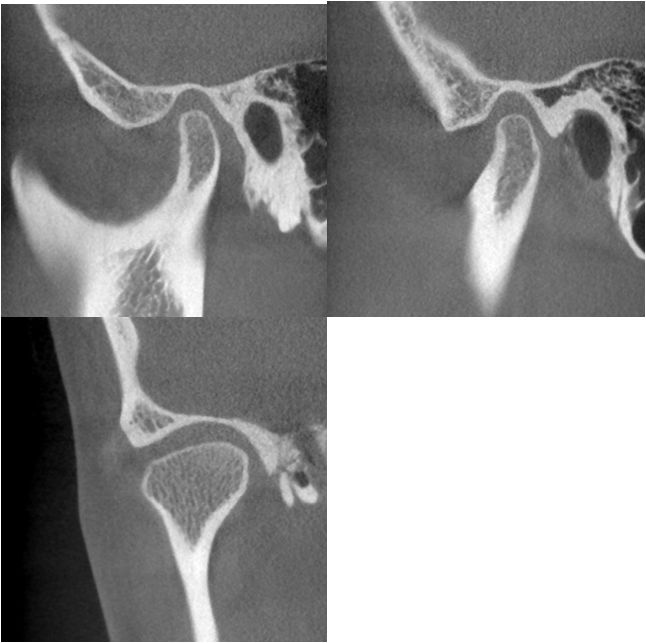

CBCT检查:

从患者双侧颞下颌关节的ct断层影像上看,右侧关节前间隙明显偏小,髁突表面骨皮质较连续但厚度较薄,右侧关节间隙较均匀,个别断面上,髁突表面的骨皮质较粗糙,不明显。左侧颞下颌关节髁突表面骨皮质模糊粗糙,厚度较薄,关节间隙较均匀。临床功能检查上,患者开口度开口型正常,双侧关节张口中期有弹响。